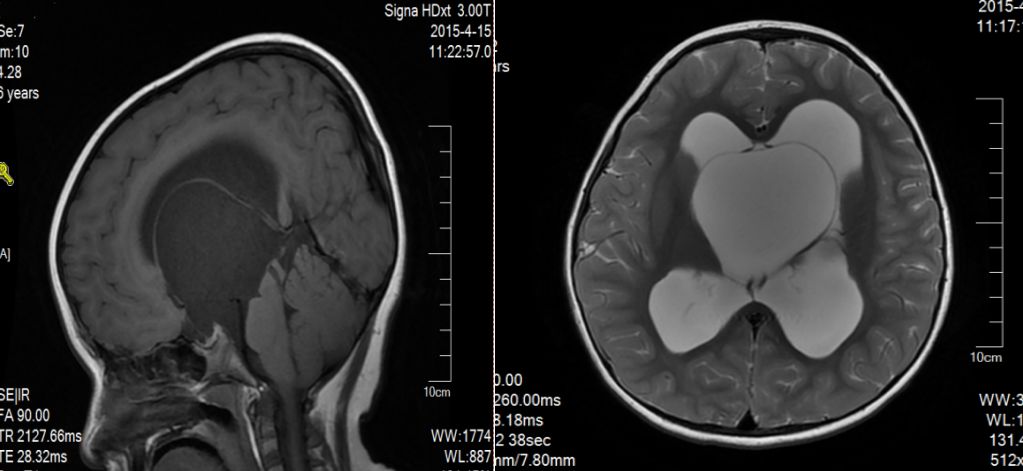

患儿,女,6岁,以“无热抽搐2次”为主诉入院。

神经科查体:一般状态差,意识模糊,Glasgow评分7分,肌张力增高,余神经科查体无明显异常。

术前影像:透明隔腔明显增宽,双侧脑室、三脑室、脚间池明显扩张、积水,周围脑实质受压,胼胝体受压变薄。弥散加权图像未见异常。中线结构居中。增强扫描未见异常强化。

术前诊断:三脑室内囊肿,幕上脑积水。

脑室内蛛网膜囊肿多位于侧脑室和第三脑室内;CT值10HU以下或MRI信号等同CSF;囊肿圆形或椭圆形,边缘光滑,壁薄,无结节;脑室扩大变形,周围无水肿。侧脑室囊肿多位于侧脑室三角区,蒂部位于室间孔周围。第三脑室囊肿常位于第三脑室前上方,室间孔开口处,一旦阻塞可引起一系列的临床症状,如头痛、头晕和呕吐等。